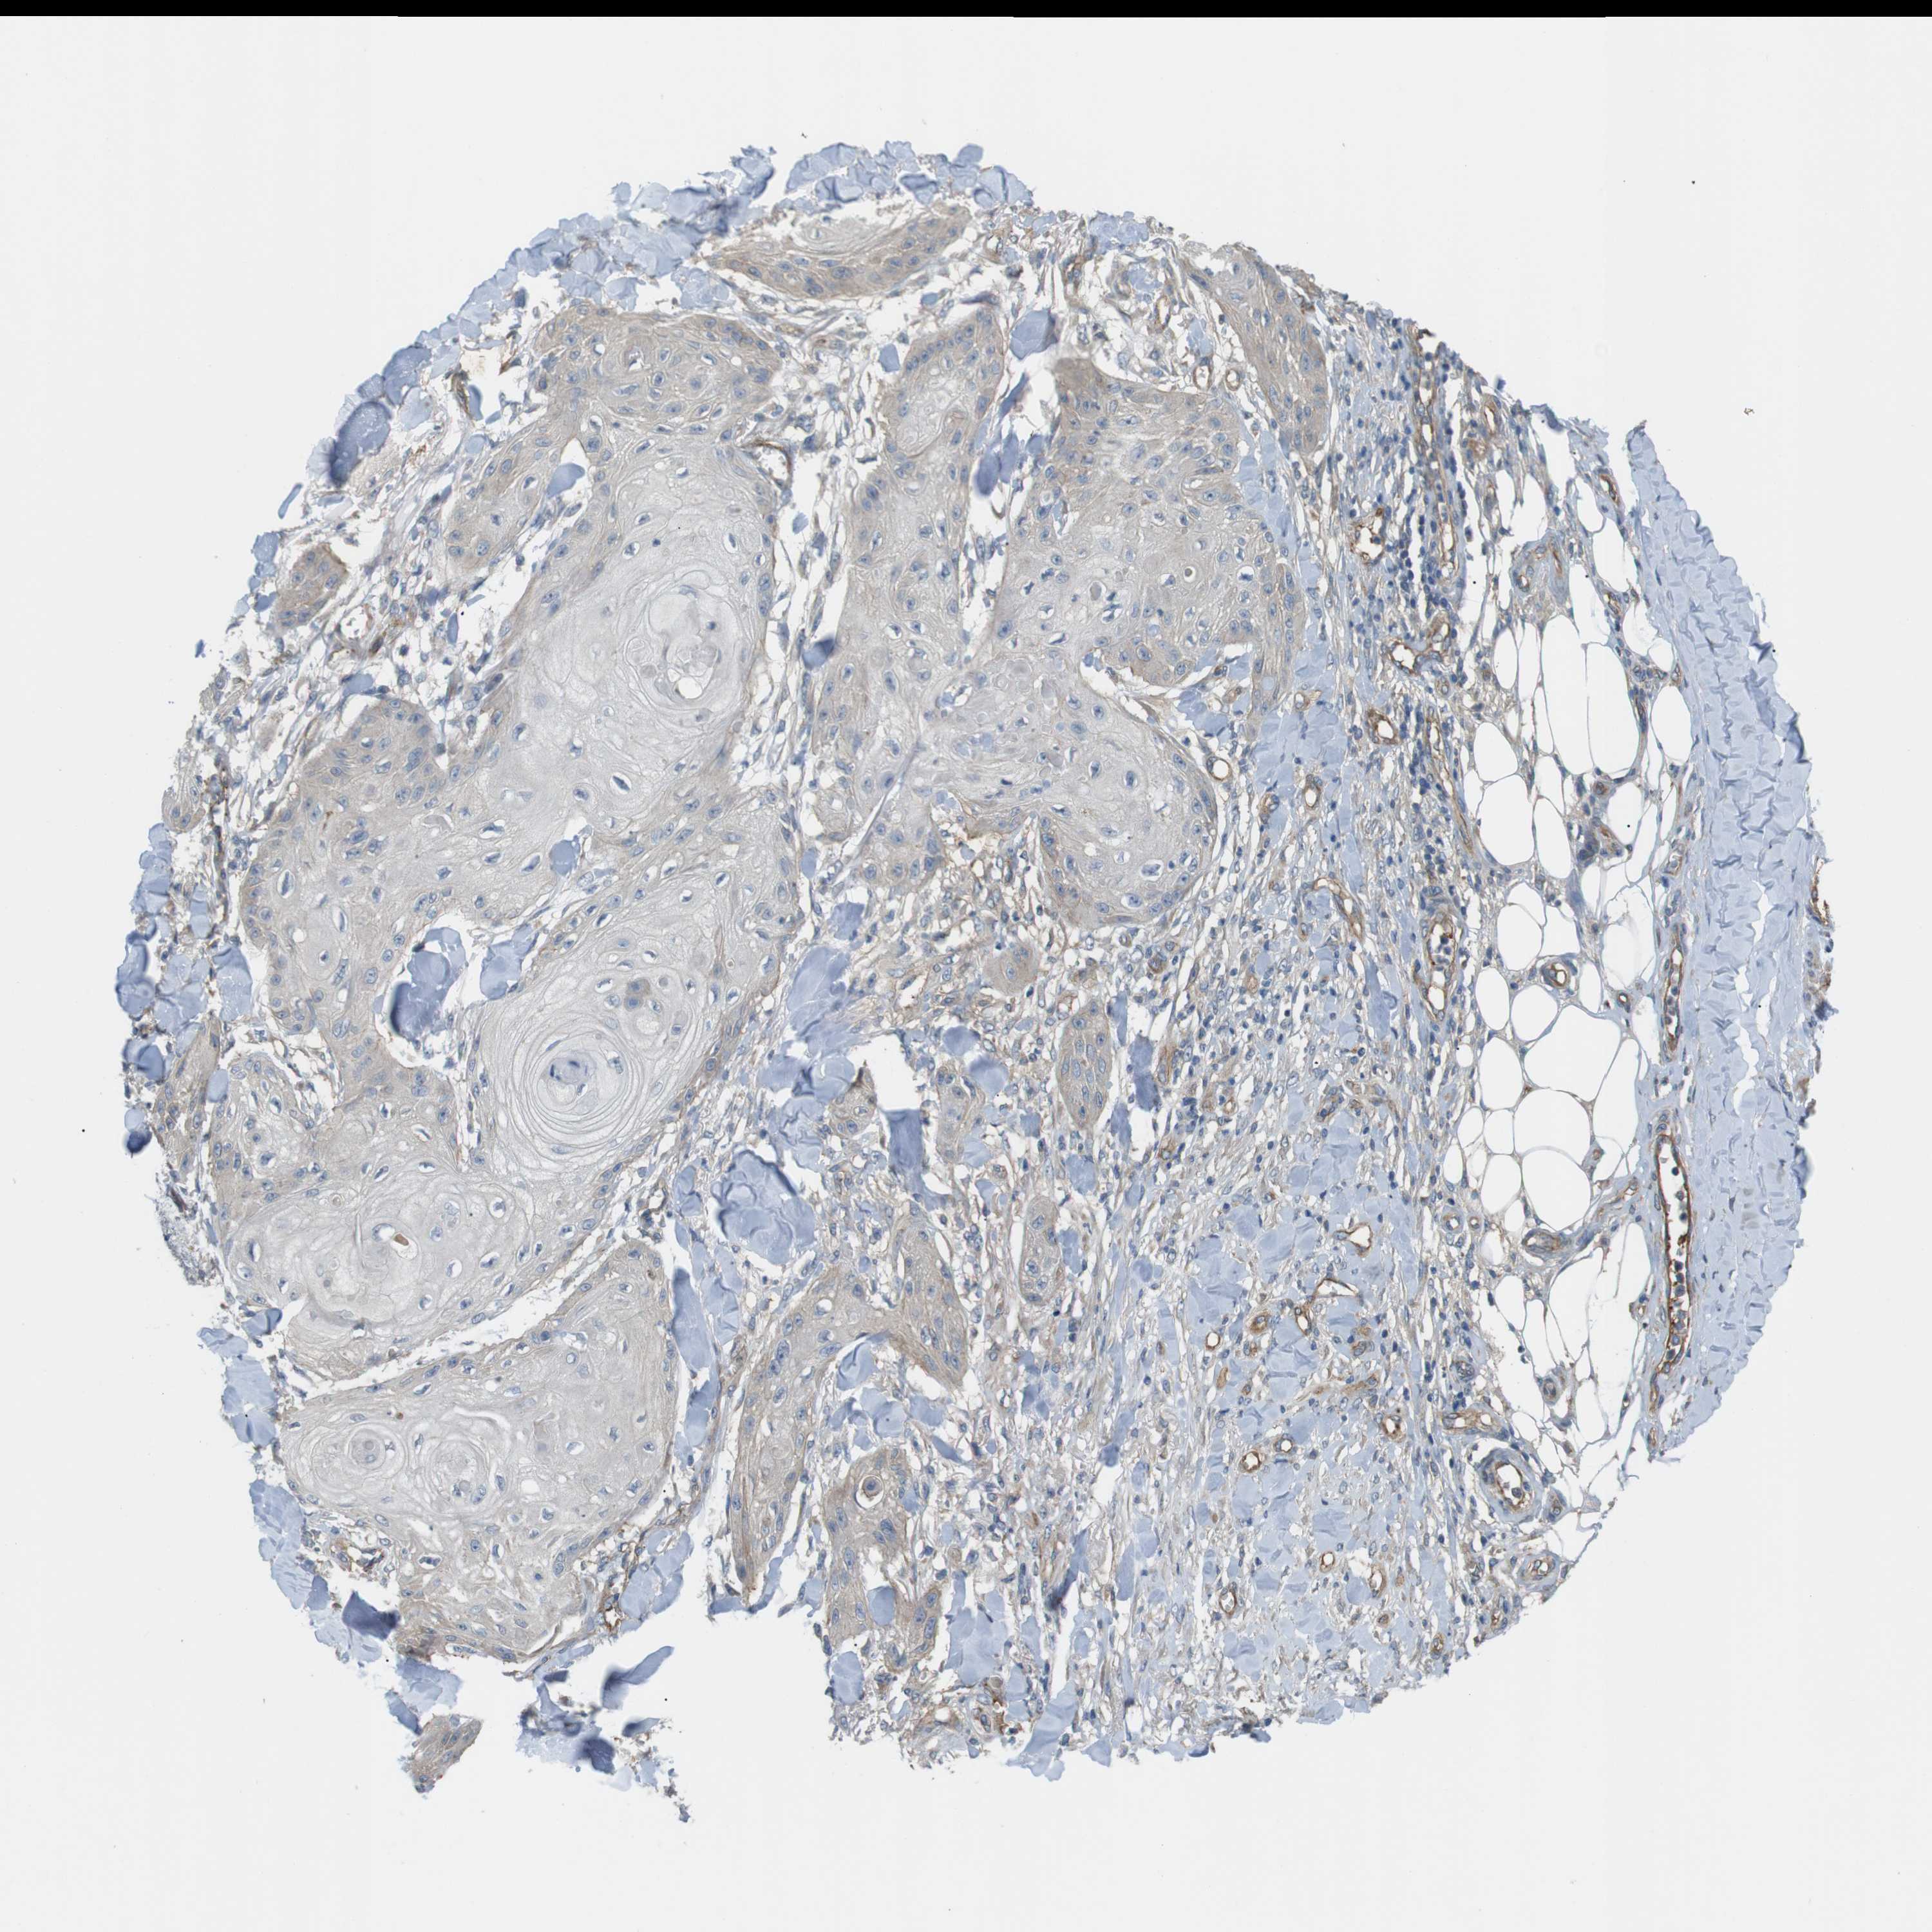

SKIN CANCER - Protein expressioni

A mouse-over function shows sample information and annotation data. Click on an image to view it in a full screen mode. Samples can be filtered based on level of antibody staining by selecting one or several of the following categories: high, medium, low and not detected. The assay and annotation is described here.

Antibody stainingi

Antibody staining in the annotated cell types in the current human tissue is reported as not detected, low, medium, or high, based on conventional immunohistochemistry profiling in selected tissues. This score is based on the combination of the staining intensity and fraction of stained cells.

Each image is clickable and will lead to virtual microscopy that enables deeper exploration of all samples and also displays staining intensity scores, fraction scores and subcellular localization as well as patient and tissue information for each sample.

Antibody HPA014788

Squamous cell carcinoma in situ, NOS

Squamous cell carcinoma, NOS

Basal cell carcinoma

Adnexal tumor, benign

Squamous cell carcinoma, metastatic, NOS